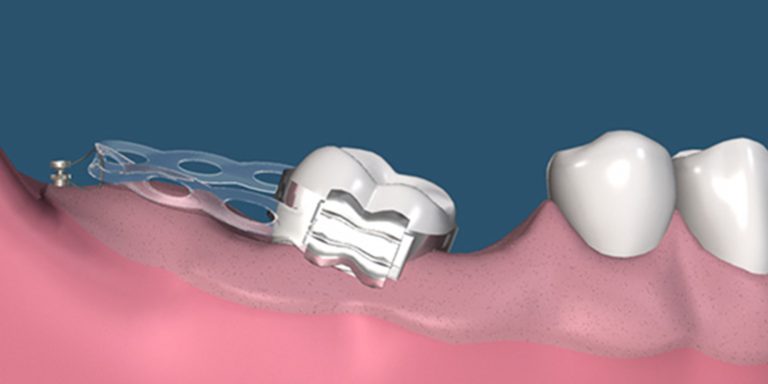

روش درمانی پل دندان

بریج دندان یا بریج دندانی زمانی استفاده میشود که یک یا چند دندان از دست رفته باشد. در این روش، دندانهای کناری تراشیده میشود و به عنوان پایه برای نصب دندان مصنوعی عمل میکنند. بریج دندان سریعتر انجام میشود و هزینه کمتری نسبت به ایمپلنت دارد، اما به دندانهای پایه فشار میآورد و ممکن است در آینده نیاز به تعویض داشته باشد.

بریج دندان سریعتر و ارزانتر از ایمپلنت است و جایگزین مناسبی برای دندان محسوب میشود. اما برای نصب آن باید دندانهای کناری تراشیده شوند که ممکن است به سلامت آنها آسیب برساند. دوام بریج دندان نسبت به ایمپلنت کمتر است و ممکن است نیاز به تعویض دورهای داشته باشد.

هزینه بریج دندان معمولاً از ایمپلنت کمتر و از ارتودنسی بیشتر است و به تعداد دندانهای پایه و جنس بریج دندان بستگی دارد. بریج دندان سریعتر انجام میشود ولی نیاز به تعویض دورهای دارد.

- مراقبت از بریج دندان:

نظافت دقیق ناحیه زیر بریج دندان با نخ دندانهای مخصوص و مراقبت از دندانهای پایه بسیار مهم است. همچنین مراجعات منظم برای بررسی سلامت بریج دندان و دندانهای اطراف توصیه میشود.

دلایل انتخاب پل دندان

بریج دندان به عنوان راه حلی سریع و اقتصادیتر برای جایگزینی یک یا چند دندان استفاده میشود. بیماران با شرایطی که نمیخواهند یا نمیتوانند ایمپلنت انجام دهند، معمولاً بریج دندان را انتخاب میکنند. البته این علت اصلی تراش دندانهای مجاور و فشار بر آنها نیاز به مراقبت و توجه بیشتر دارد. بریج دندان برای کسانی مناسب است که استخوان کافی برای ایمپلنت ندارند یا شرایط جراحی مناسب نیست.

در مقابل، بریج دندان که به دندانهای مجاور متصل میشود، قادر به تحریک استخوان فک نیست. به مرور زمان ممکن است باعث تحلیل استخوان در ناحیه بدون دندان شود. این روش سریعتر و هزینه کمتری دارد ولی دوام آن نسبت به ایمپلنت کمتر است. علاوه بر این، بریج دندان به دندانهای سالم مجاور فشار وارد کرده و ممکن است به آنها آسیب برساند.

بریج دندانها معمولاً بین ۷ تا ۱۵ سال دوام دارند. برای نصب نیاز به تراش دندانهای مجاور دارند که این امر ممکن است به سلامت آنها آسیب برساند و باعث کاهش ماندگاری کلی درمان شود. ارتودنسی اما یک روش درمانی برای اصلاح ناهنجاریها و مرتبسازی دندانها است و جایگزین دندان نمیباشد، بنابراین مقایسه ماندگاری آن با ایمپلنت و بریج دندان معنایی ندارد.